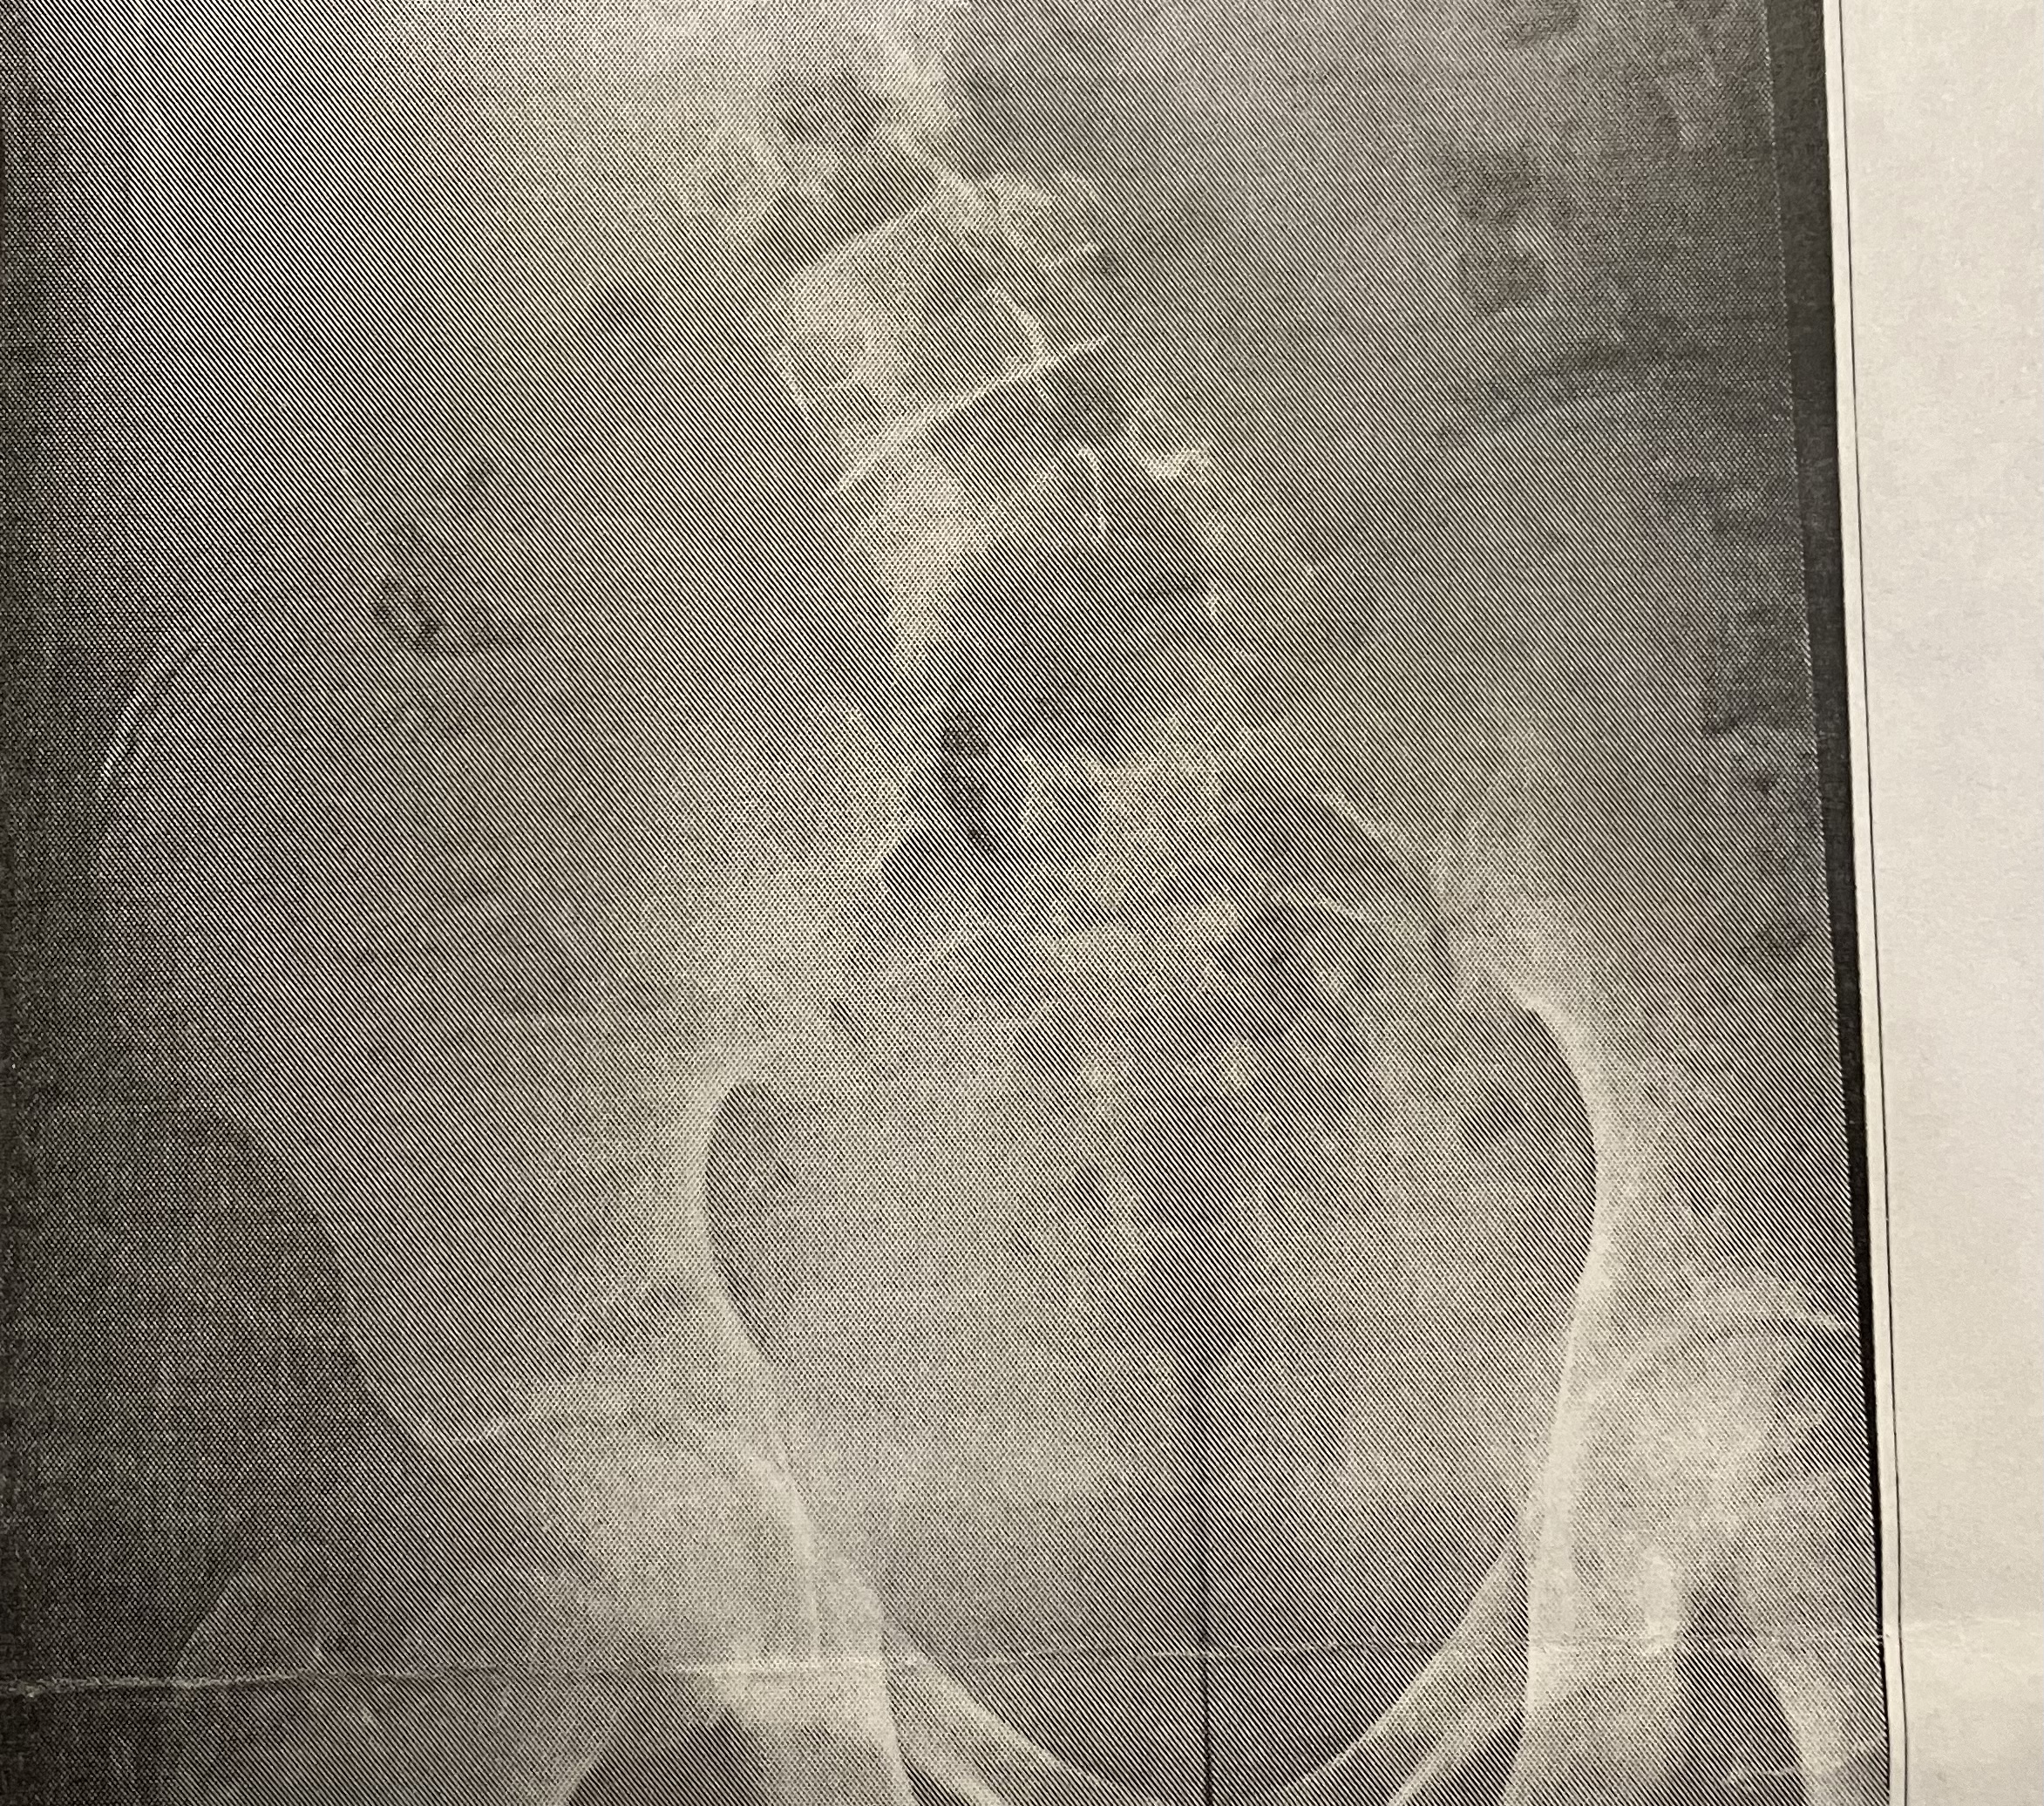

My doctor said it’s still open

is it open ?do you have an xray of ur wrist

im almost 6'2looks closed. its over op

I have slight scoliosis too lmfao, from what I can tell they’re closed